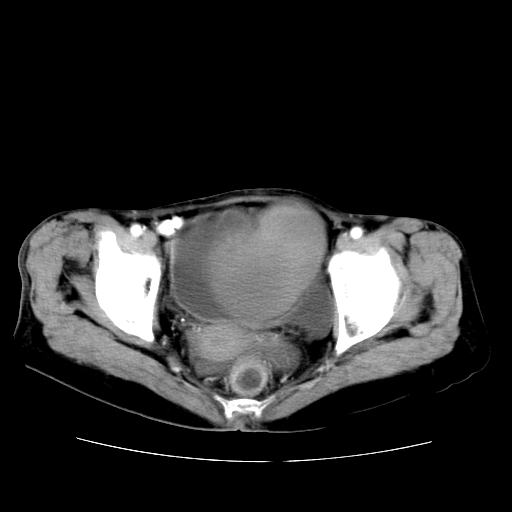

女性,72岁。

主诉下腹部坠痛不适1年余。

子宫增大如孕3月大小,质软,活动可,无压痛。

b超提示:盆腔(子宫前方)低回声团块。

临床诊断:盆腔肿块查。

1、这个肿瘤密度均匀,增强后轻中度均匀性强化,与左侧附件关系密切,肿瘤边缘光整、清晰。

2、左侧卵巢增大呈8×8×10cm大小,实性,表面光滑,边清,左侧输卵管爬行于左卵巢上,子宫萎缩。右输卵管、卵巢萎缩。

左侧卵巢纤维瘤(性索间质肿瘤)

卵巢纤维瘤为良性卵巢性索间质肿瘤,常为单侧发病,当合并腹水或胸腹水时称麦格斯(meigs)综合征,肿瘤切除后胸腹水可消失。ct表现为盆腔内边界清楚的圆形或椭圆形肿块,常有分叶或不规则;肿瘤多为实性,少数为囊性、囊实性,完全囊性者可见壁结节。实性部分与子宫等密度;增强扫描常为轻度强化或几乎不强化。